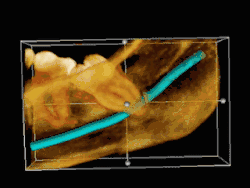

Risk factors of inferior alveolar nerve damage

Temporary and permanent inferior alveolar nerve (IAN) damage is a known complication of the surgical removal of impacted lower third molars, happening in 1 in 85 patients and 1 in 300 extractions, respectively. Studies have shown that certain risk factors may increase the likelihood of IAN damage. Proximity of the impacted third molar root to the mandibular canal, which can be seen in radiographs, has been shown to be a high-risk factor for IAN damage. Alongside this, the depth of impaction of the tooth, surgical technique and surgeons experience are all contributing risk factors for IAN damage during this procedure. Careful case-by-case consideration is crucial to avoid this risk.[44]